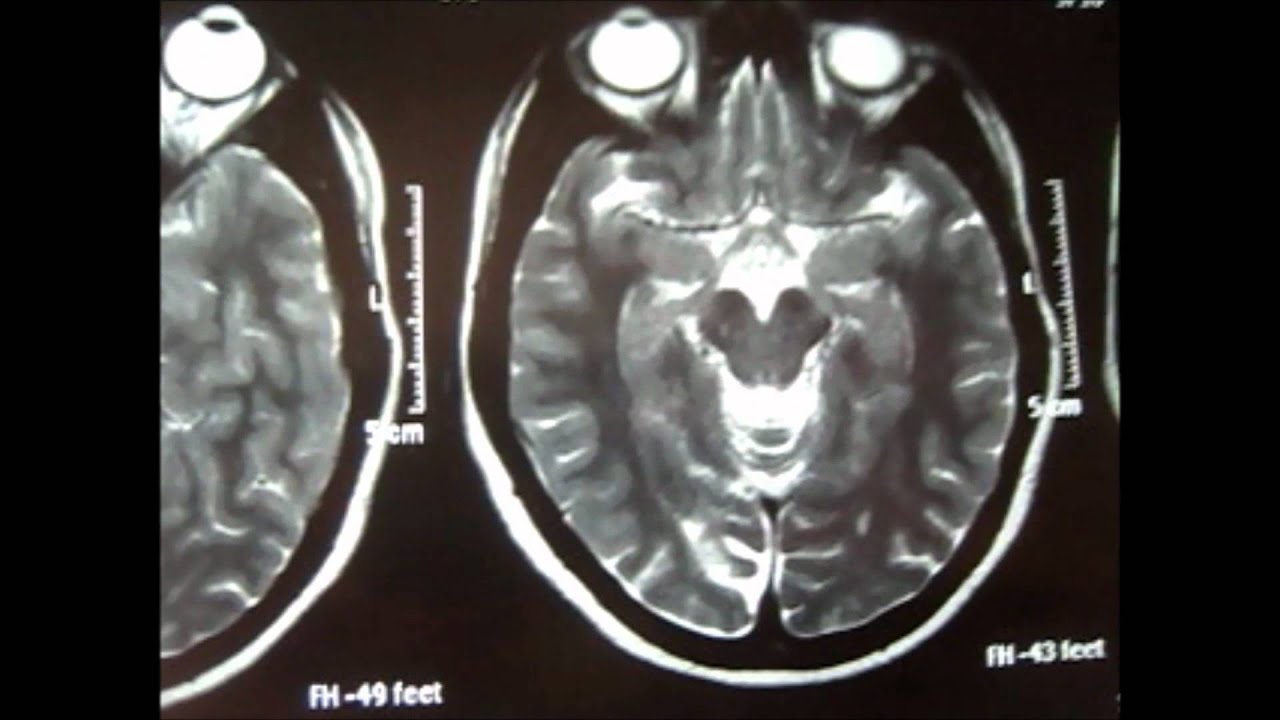

Images of Infarction Brain

Photos of Infarction Brain

Infarction Brain Photos

Infarction Brain Pictures

Brain Infarction CT Scan - YouTube

You can see CT scan of a patient showing brain infarction. ... View Video